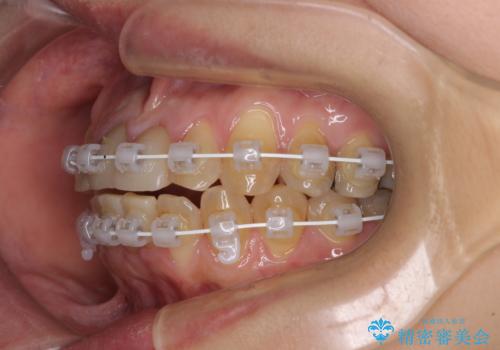

- 矯正装置

- 審美装置

舌の突出癖により治療期間中に開咬となり、治療が長引きましたが、口元も治療前よりも引っ込めることができ、すっきりとした仕上がりとなりました。